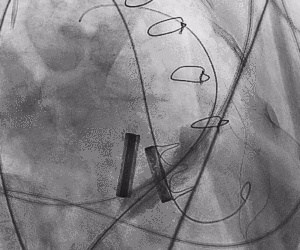

手术过程

1.术中经股静脉入路,送入指引导管、导丝,成功跨瓣,建立导丝轨道。

2.进行预扩张。球囊打开时未见明显腰征,预扩张球囊顺利打开梗阻瓣膜。